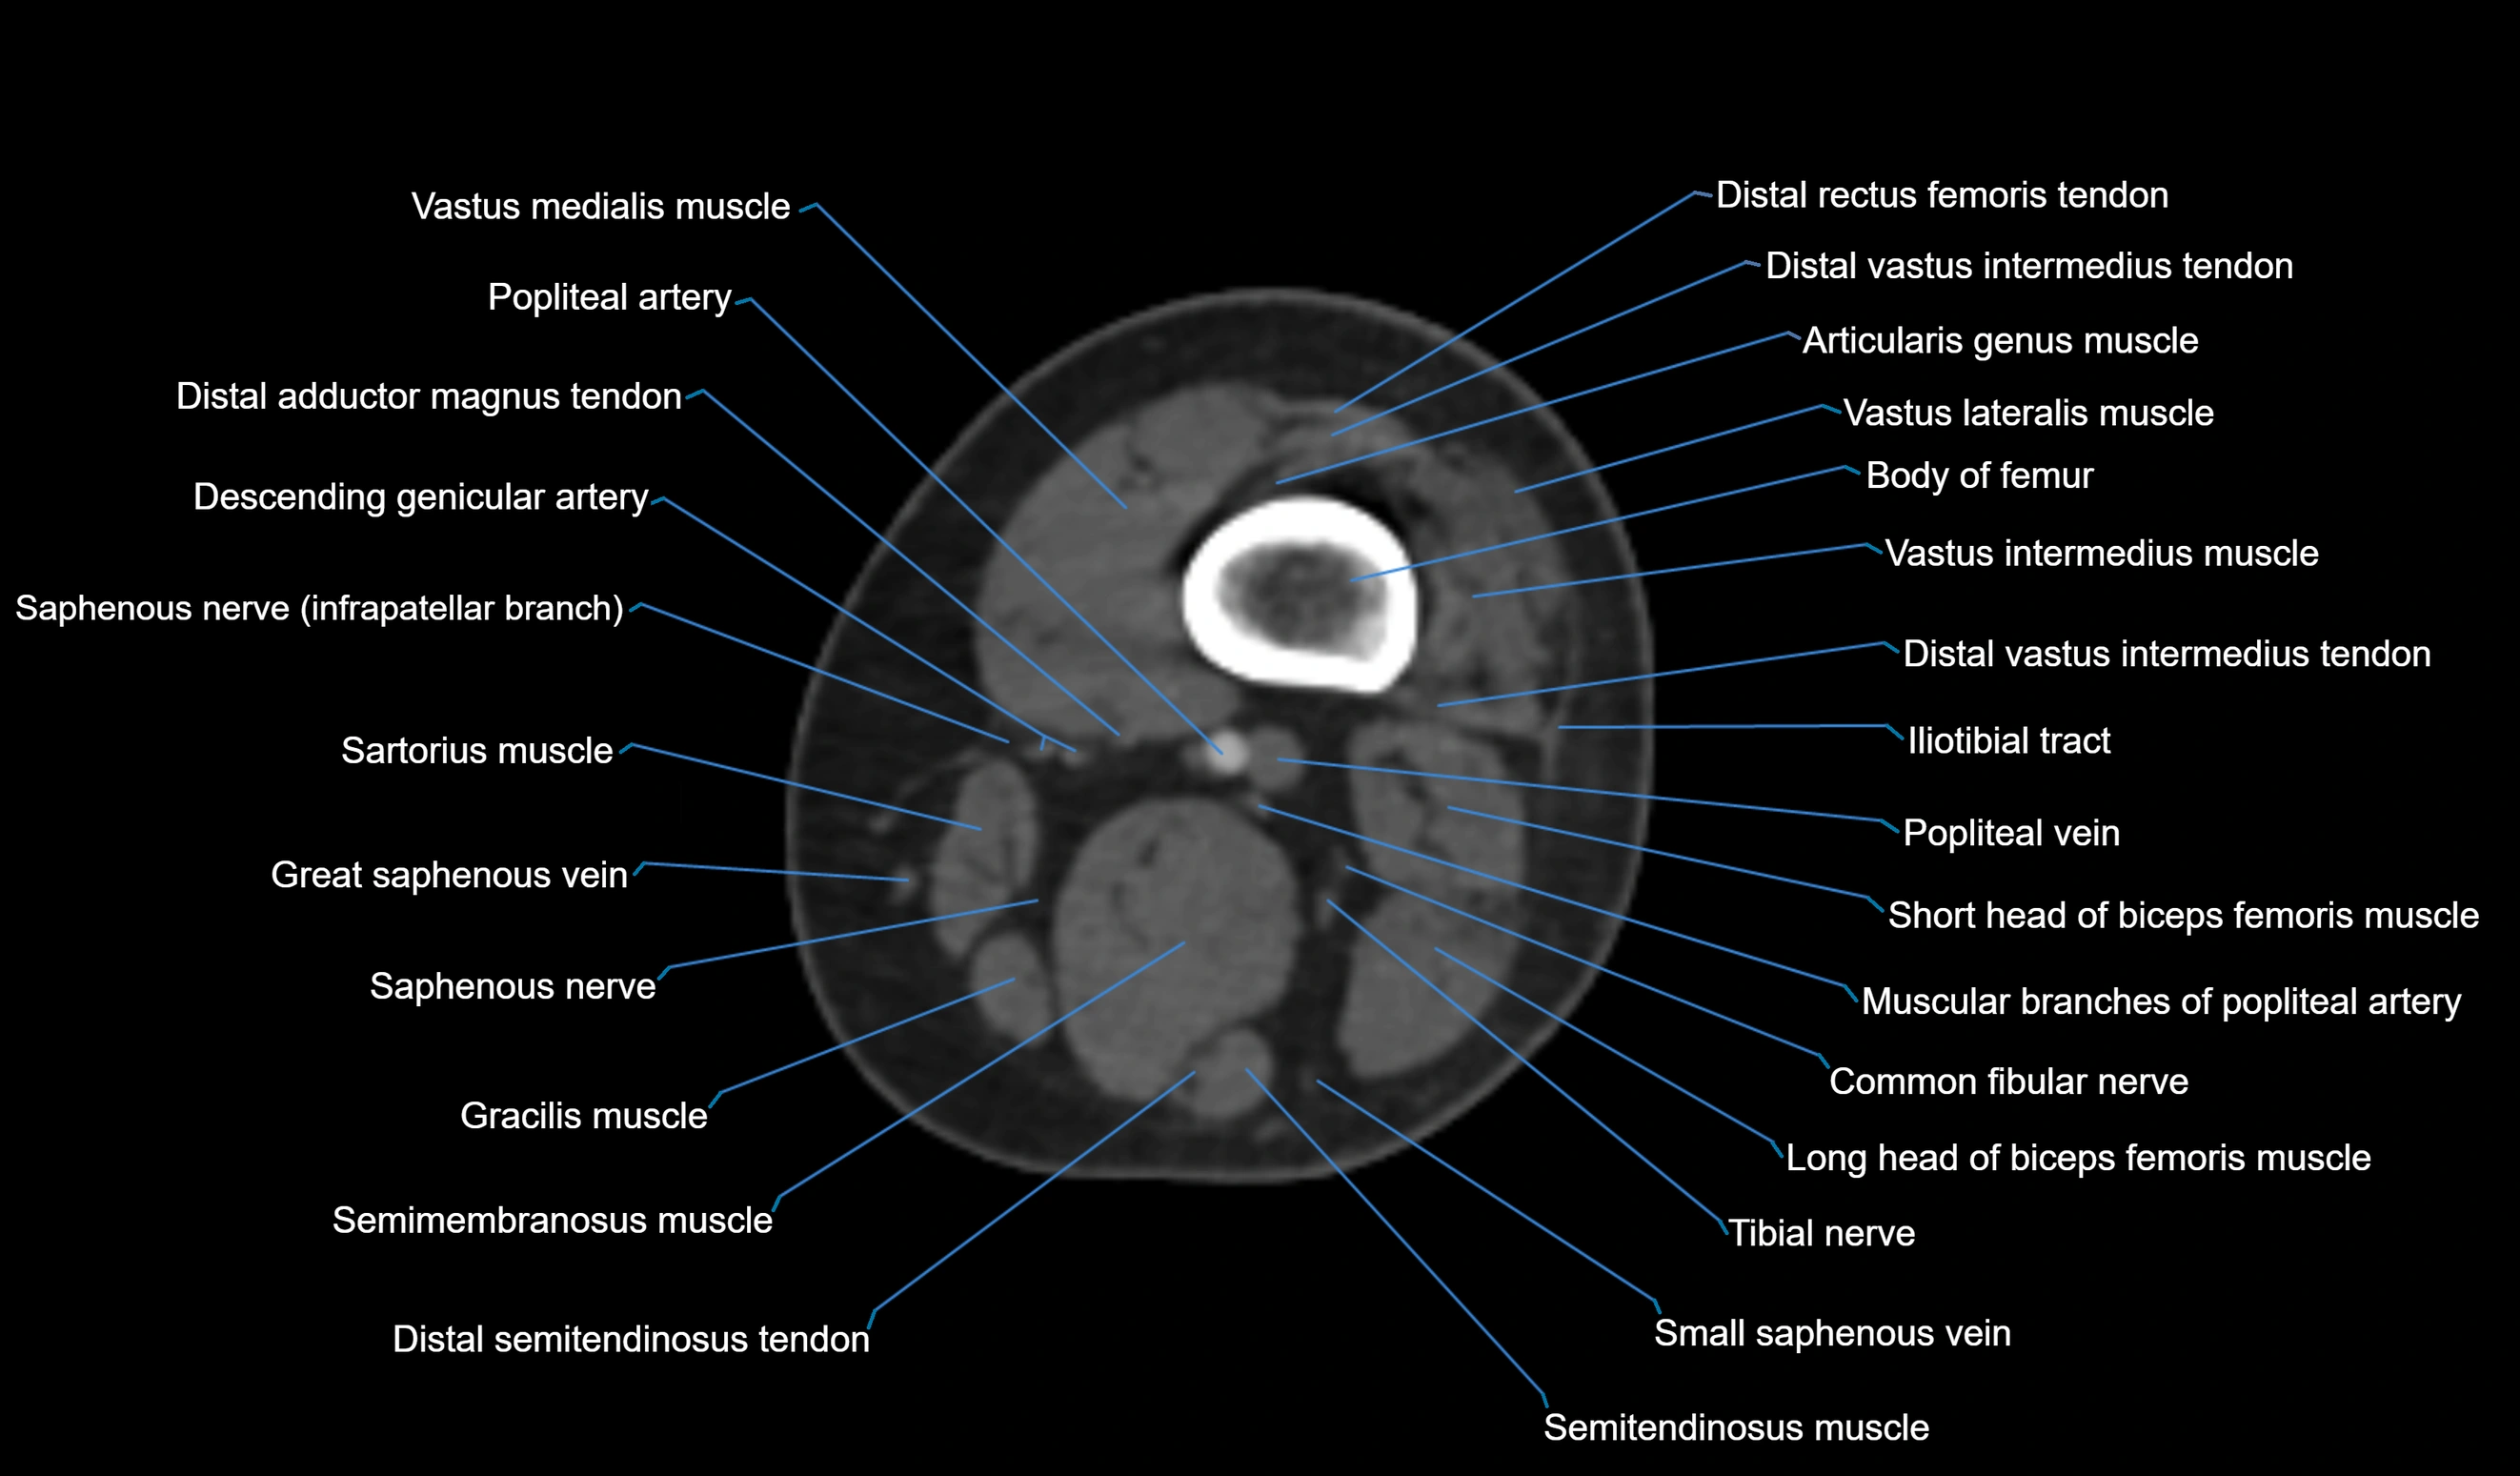

- Body of femur

- Common fibular nerve

- Distal adductor magnus tendon

- Distal rectus femoris tendon

- Distal semitendinosus tendon

- Distal vastus intermedius tendon

- Distal vastus lateralis tendon

- Popliteal artery

- Popliteal vein

- Saphenous nerve

- Sartorius muscle

- Semimembranosus muscle

- Semitendinosus muscle

- Small saphenous vein

- Tibial nerve

- Vastus lateralis muscle

- Vastus medialis muscle